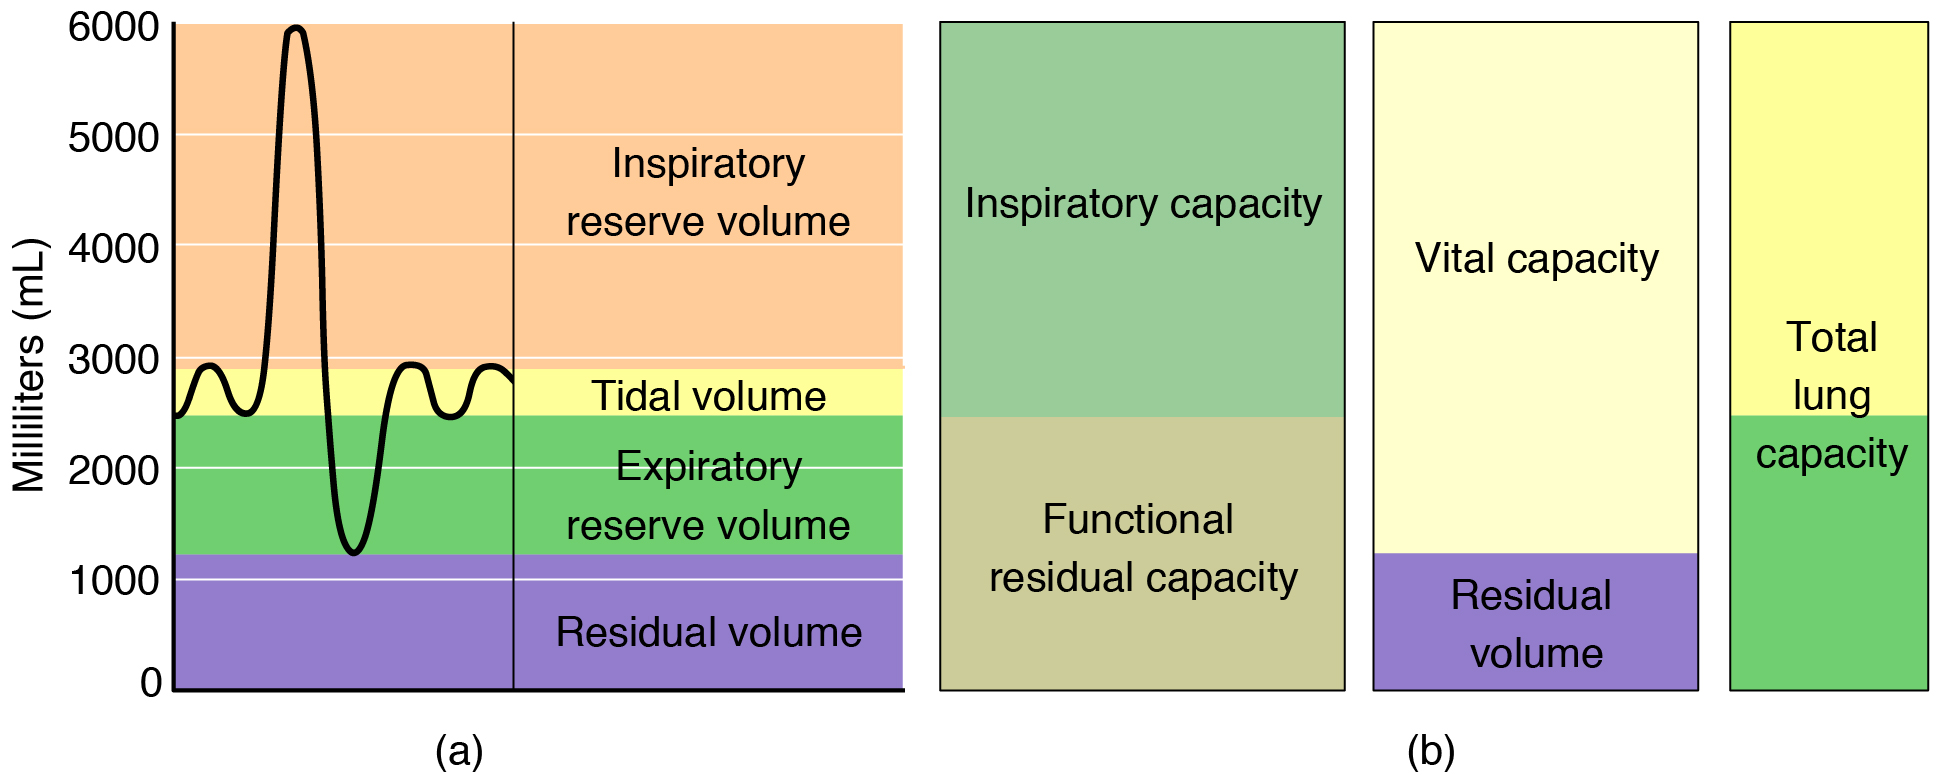

Type III: – type III respiratory failure usually takes place in the peri or post operative period where the abdominal wall mechanics are abnormal. Patients usually have progressive atelectasis due to inadequate functional residual capacity leads to . The clinical progression of type III respiratory failure usually leads to either type I or type II respiratory failure.

- Peak Expiratory Flow – this test can be done to measure the severity of airway obstruction.